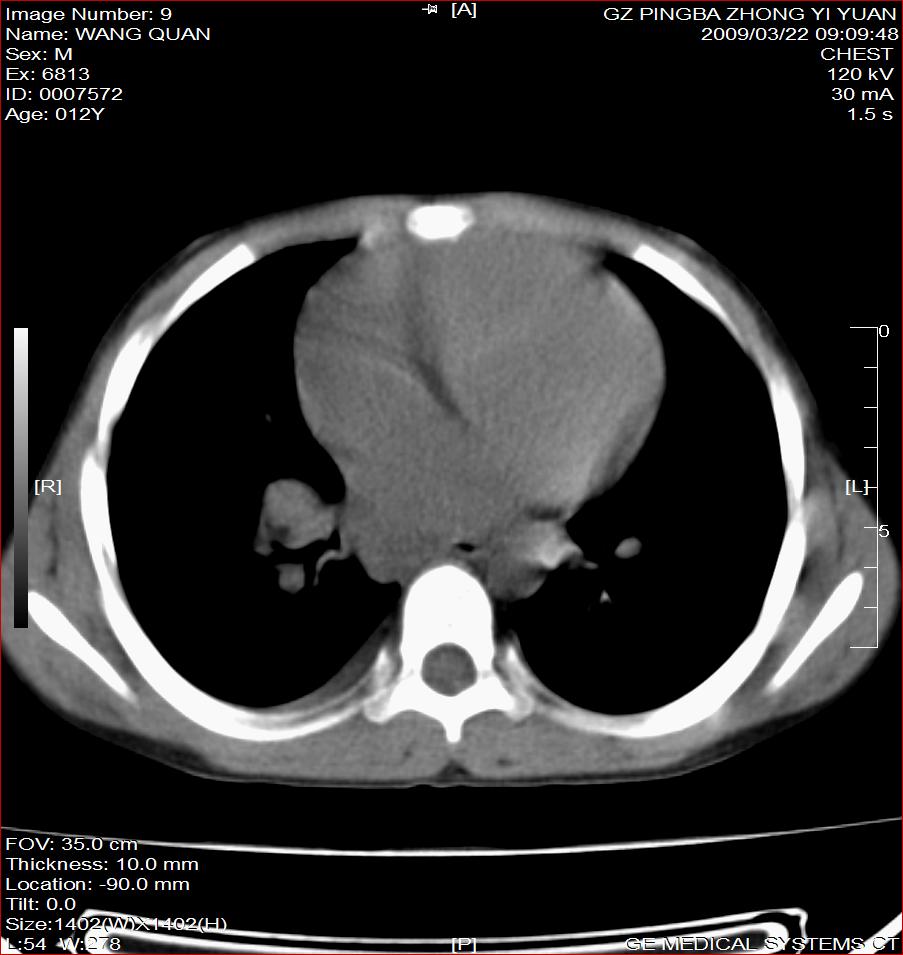

以下是引用随光逐影在2009-3-23 8:12:00的发言:[br]1)右肺门及纵隔淋巴结结核。2)两肺急性血行播散型肺结核可能。3)右侧支气管内膜结核?建议必要时行纤支镜检查。4)右侧少量胸腔积液。